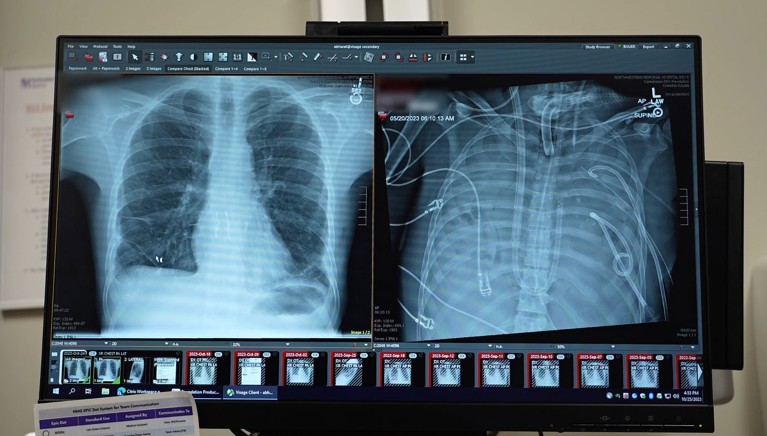

在接受人工肺治疗前,这名男子因流感病毒感染而患上了急性呼吸窘迫综合征——一种肺部无法吸收足够氧气的危及生命的疾病。随后他被接上了呼吸机,但又感染了耐药性铜绿 假单胞菌。感染导致他部分肺部充满脓液,并引发了感染性休克,此时他的心脏和肾脏开始衰竭。